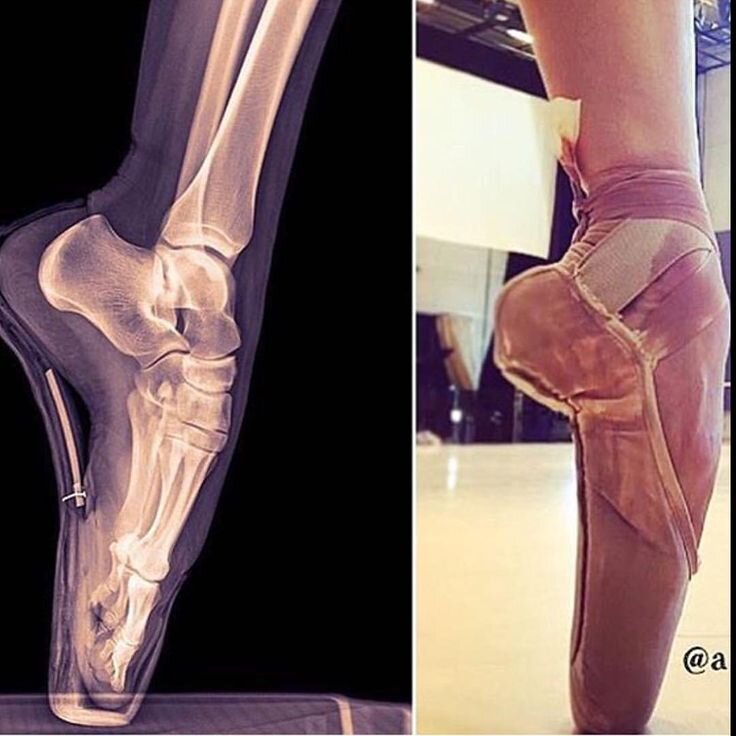

Секрет на самом деле именно в устройстве обуви. Смех смехом, но это в некоторой степени колодки для стопы. Задача пуанта, так обхватить стопу в самой ее широкой части, чтобы передать вес танцовщицы по конструкции коробки (часто называется еще «стакан») на пятак, на котором собственно и балансирует исполнительница в танце. При этом самого пятака внутри обуви обычно только касаются самым/и длинными пальцами, но ни в коем случае не стоят на них всем весом (осознанно, разумеется).

В чем разница? Все просто. Работать на пуантах возможно только на полном пятаке со стремлением перейти к передней грани. Ладьевидная и таранная кости находятся над и кпереди от большого пальца.

Также помним, что на самом деле пальцы в пуантах вес тела нести не должны. Проваливаться в "коробку" и вставать на фалангу нельзя, касаться - можно.